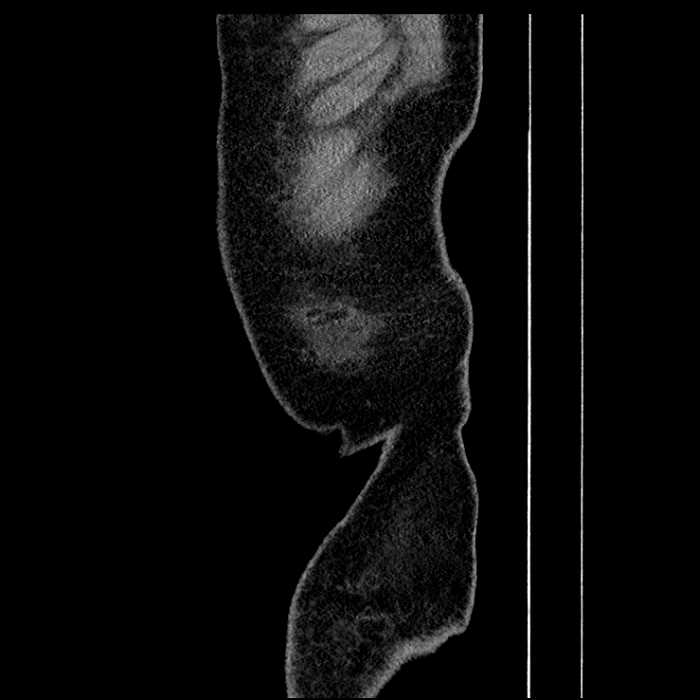

• Large fluid density structure in hepatic segments 7 and 8 measuring 10 x 7 x 7 cm with internal septation and circumferential ill-defined low density compatible with edema

• Clearly marginated fluid density structure in segment 7 and several other scattered tiny hypodensities, which likely represent cysts

• Hepatic abscess

Acute sigmoid diverticulitis complicated by a small contained perforation and a large abscess in the right hepatic lobe. Additional small subcapsular abscesses along the anterior margin of the left hepatic lobe.

• The classic CT imaging appearance is a double target sign with internal low density surrounded by an internal enhancing rim (capsule) and a low density external rim (edema)

Hepatic abscess showing the double target sign with low density internally surrounded by a thin inner enhancing rim (red arrow) and ill-defined outer low density rim (yellow arrow). Blue arrow indicates an internal septation. Red arrows: additional smaller subcapsular abscesses. Red arrow: focal contained perforation associated with diverticulitis.